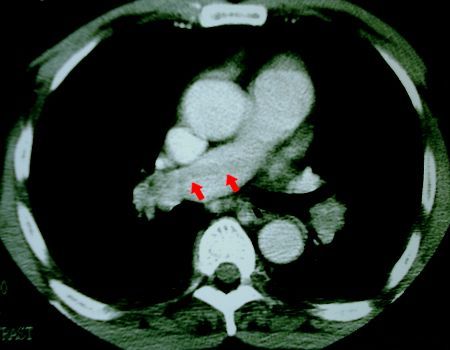

We recently encountered such a case. A sixty-one year old man developed a massive pulmonary embolus ten days after craniotomy for a brain biopsy. The pulmonary embolus was documented on spiral computerised tomography (Figures 1 and 2).

Spiral CT of pulmonary artery showing thrombus in

left pulmonary artery

Fig 1. Spiral CT of patient showing large thrombus (arrowed) within the left pulmonary artery